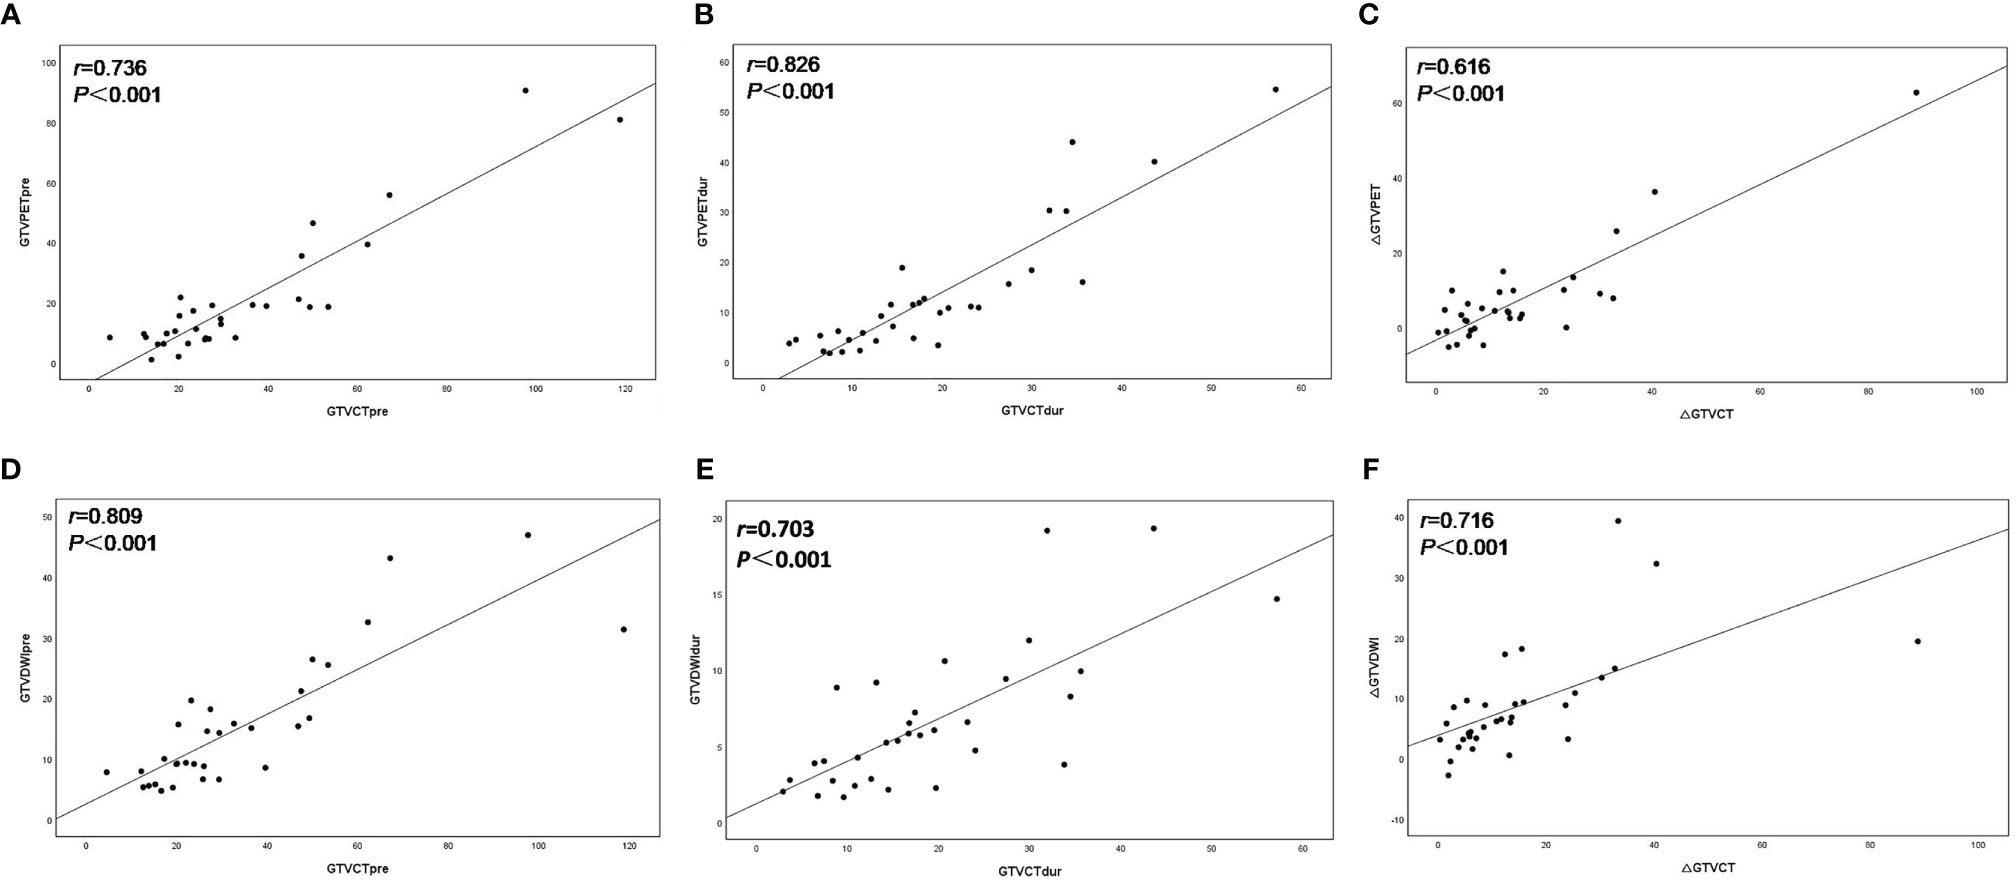

The volume of GTVCTpre was 26.34 (4.50–118.71) cm3, leading to a significantly positive correlation with both GTVPETpre (Figure 1A) and GTVDWIpre (Figure 1D) (r = 0.763 and r = 0.809, both p < 0.001). The volume of GTVCTdur was 16.74 (2.92–57.13) cm3 and exhibited a significant positive correlation with both GTVPETdur (Figure 1B) and GTVDWIdur (Figure 1E) (r = 0.826 and r = 0.703, both p< 0.001). Similarly, the relative changes in the volume of PET-CT and DW-MRI (∆GTVPET, ∆GTVDWI) before and during RT demonstrated a significantly positive correlation with that of CT (∆GTVCT) before and during RT (r = 0.616 and r = 0.716, both p < 0.001) (Figure 1).

Figure 1 Scatter plots of correlation between the target volume delineated on18F-FDG PET–CT (GTVPET) and DW-MRI (GTVDWI) and on the corresponding CT (GTVCT) before and during radiotherapy. The best-fit line is shown as the solid line for each scatterplot. (A) GTVPETpre versus GTVCTpre; (B) GTVPETdur versus GTVCTdur; (C) ΔGTVPET versus ΔGTVCT; (D) GTVDWIpre versus GTVCTpre; (E) GTVDWIdur versus GTVCTdur; (F) ΔGTVDWI versus ΔGTVCT.